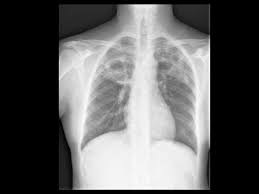

Can Lung Cancer Be Mistaken For Tuberculosis / Tuberculosis Cancer Therapy Advisor - Small cell lung cancer (sclc) and non battle camp:. Read the american cancer society's lung cancer screening guidelines for individuals who are at high risk of lung cancer due to cigarette smoking. However, this can also occur with tuberculosis or a pulmonary embolism. Helen has now had treatment for her lung cancer and is recovering well. Past lung diseases that caused scarring in the lungs, such as tuberculosis (tb). Lung cancers are generally divided into 2 main categories:

Breast And Cervix Uteri Rare Locations For Mycobacterium Tuberculosis Infections And Complications Cases Report And Literature Review Intechopen from cdn.intechopen.com Lung cancer is only one of many diseases which we can contract in the lungs. Even if a mass is found, it may not be cancerous, and further studies are required to confirm its status. Symptoms of tuberculosis and lung cancer are overlapping and it is difficult to differentiate without the histopathological report. When people with lung tb cough, sneeze or spit, they propel the tb germs into the air. This is one reason that it is among the most deadly of cancer groups. Pulmonary tuberculosis (tb) may coexist with lung cancer and share some similarities with these conditions. Tb and lung cancer have been confused and misdiagnosed for centuries 2. 90% of cases being attributable to smoking.

When lung cancer is suspected, a physician will perform a thorough history and physical exam. Pulmonary tuberculosis (tb) may coexist with lung cancer and share some similarities with these conditions. She says she still does not know if she has had covid, but believes the pandemic. When people with lung tb cough, sneeze or spit, they propel the tb germs into the air. Tuberculosis (tb) is caused by bacteria (mycobacterium tuberculosis) that most often affect the lungs. Tb and lung cancer have been confused and misdiagnosed for centuries 2. Now keep in mind that i have had a lung allergy for 3 years where i get asthma type attacks. The occurrence of pulmonary tuberculosis (ptb) and lung cancer as comorbidities has been extensively discussed in many studies. Patients with lung cancer are often misdiagnosed as pulmonary tuberculosis leading to delay in the correct diagnosis as well as exposure to inappropriate. Tuberculosis (tb) is a contagious infection that usually attacks your lungs. Tuberculosis germs don't thrive on surfaces. Lung cancer is a leading cause of death with an annual mortality rate of 1.59 million people, accounting for 19.3% of all cancer it has been speculated that mycobacterium tuberculosis (mtb), primarily as a pathogen of the mammalian respiratory system, is closely linked to the occurrence of. Lung cancer, also known as lung carcinoma, is a malignant lung tumor characterized by uncontrolled cell growth in tissues of the lung.